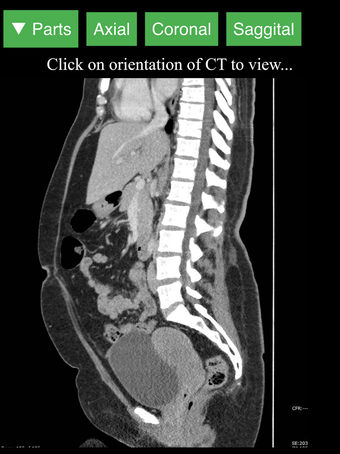

Radyoloji BT Görüntüleyicisi, doktorlar, tıp öğrencileri, radyoloji teknisyenleri ve diğer sağlık profesyonellerinin insan vücudu ve anatomisi hakkında daha fazla bilgi edinmelerine yardımcı olan faydalı bir araçtır. Uygulama, en önemli insan vücut parçalarının detaylı kesit çizimlerini içerir. Ayrıca, anatomiyi daha iyi görmek için görüntü etrafında döndürme, yakınlaştırma ve kamera hareket ettirme imkanı sunan etkileşimli bir 3D model içerir.

İnsan vücudu hakkında daha fazla bilgi edinmenize yardımcı olacak bir araç arıyorsanız, Radyoloji BT Görüntüleyicisi harika bir seçimdir. Detaylı çizimler ve etkileşimli bir 3D model içerir.